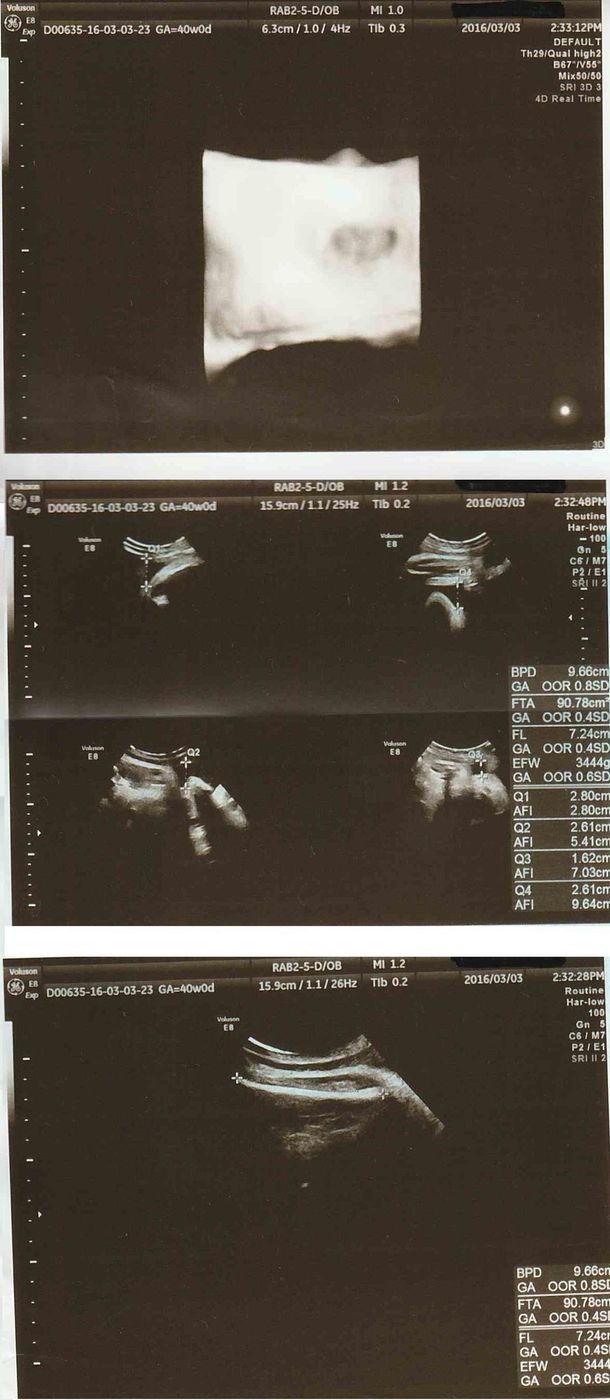

テーマ: ふー妊娠6ヶ月~7ヶ月* 先週の金曜日に初 4Dエコー に行ってきました ウチの病院は4Dはいつもの先生じゃなくって、 専任の技師さんが担当してくれるのですが、 予約が平日の午後しかなくって、ダンナと休暇エコーの写真だけでなく4dもやってる病院で、健診がすごく楽しみでした。 顔がエコーに映っていないと、写真はもらえませんでした。 果たして胎児は男の子なのか、女の子なのか。エコーでいつ、どんなふうに性別がわかるの? オービス 1 :名無しさん:(日) IDd//URnS5net って、速度超過で通り過ぎても、稼働しない場合があるん

こんな感じで、初めての4Dエコーにとても感動して親バカが炸裂しました。 臨月になると、赤ちゃんにも脂肪がついてぎゅうぎゅうで入っているようで。 あの日見た美少女はどこへ? と戸惑いながらも冷静さを取り戻しました(笑) 実際生まれてきお子さんの可愛いエコー写真見せて下さい♡ 私のお気に入りのエコー写真です。 女の子です♡ 4Dエコーと同じ顔で産まれてくるのかどうか楽しみです٩ (ˊᗜˋ*) 2月22日 お気に入り 女の子 エコー写女の子は妊娠7ヶ月で判明が多い妊娠24週~26週のエコー写真 妊娠7ヶ月頃になると、多くの産院でエコー検査にて性別を調べてくれるようになります。 (産院の方針や妊婦の状況にもよる) この頃になると男の子のシンボルがエコーで見えない